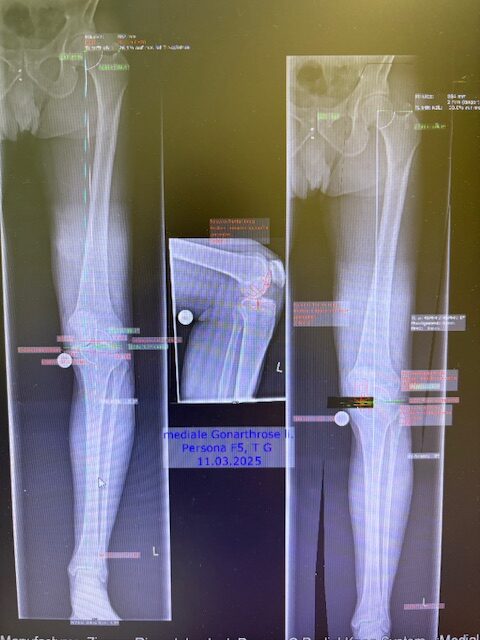

Ο προεγχειρητικός ψηφιακός σχεδιασμός

Πραγματοποιήθηκε απεικόνιση και ψηφιακός σχεδιασμός της επέμβασης, ώστε να προσδιοριστεί με ακρίβεια το μέγεθος και η θέση των προθέσεων. Ο στόχος ήταν να αποκατασταθεί η φυσιολογική μηχανική του γόνατος, διατηρώντας ανέπαφα τα υγιή τμήματα της άρθρωσης, τους συνδέσμους και τους γύρω μυς.